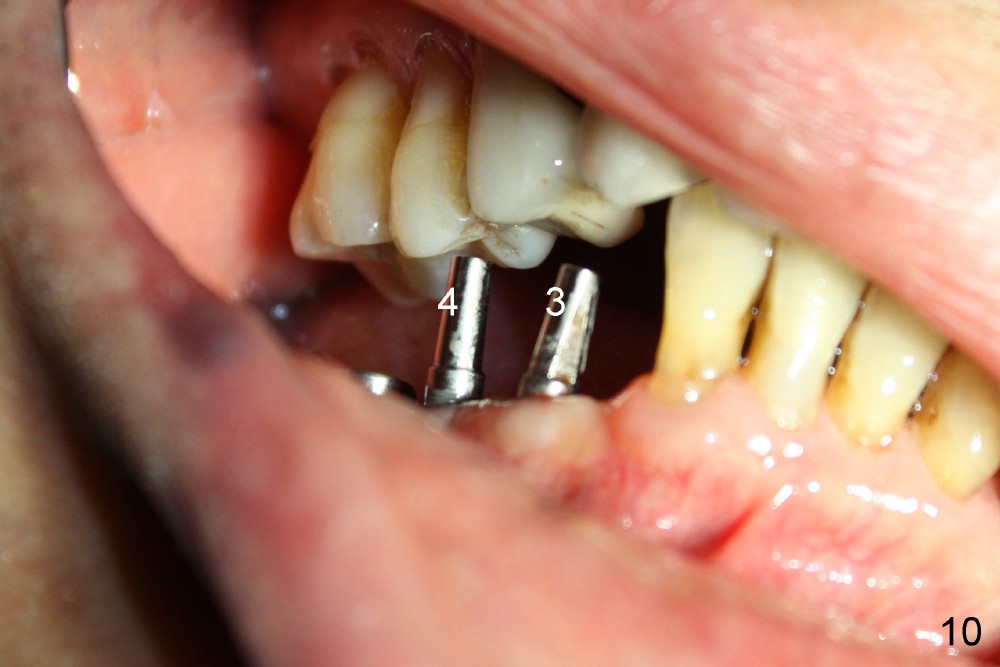

Four months after implantation, the gingiva around these four implants is healthy (Fig.8).  Healing cuffs are placed over the implants #5 and 6 (Fig.9).  The trajectory for the one piece implants is within normal limit relative to the opposing dentition (Fig.9,10).